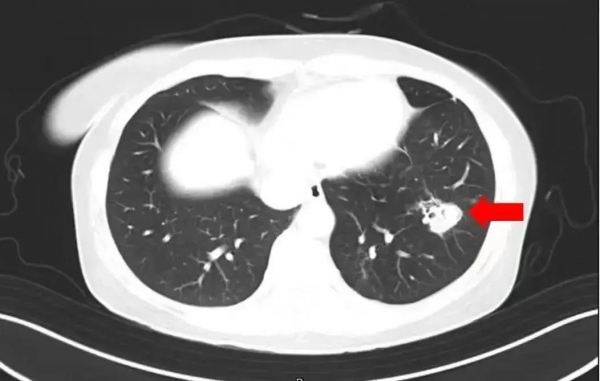

经检查,医生在玲玲的脑部影像上看到了触目惊心的一幕--20多个空洞散布在大脑组织中,就像被什么东西啃食过一般。

"非常罕见,这是烟曲霉感染导致的脑组织破坏。"医生解释道。真菌通过呼吸道进入血液,最终侵袭至大脑。